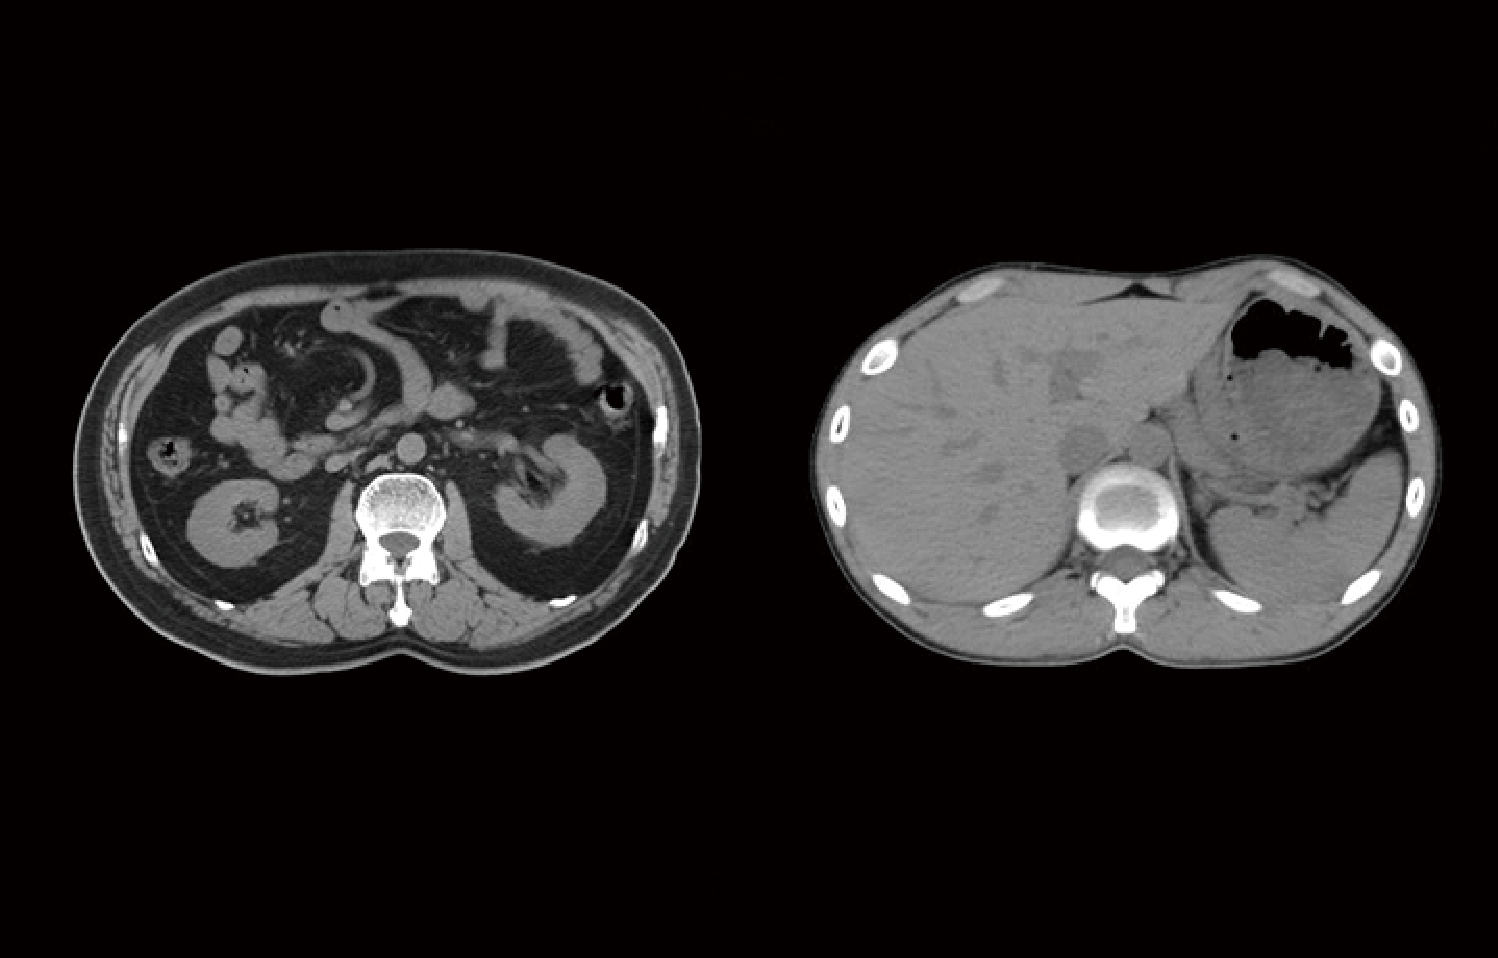

La matriz de reconstrucción de 1024*1024 amplía los datos de la imagen cuatro veces. Combinado con imágenes de corte fina, incluso las lesiones más invisibles son claramente visibles.